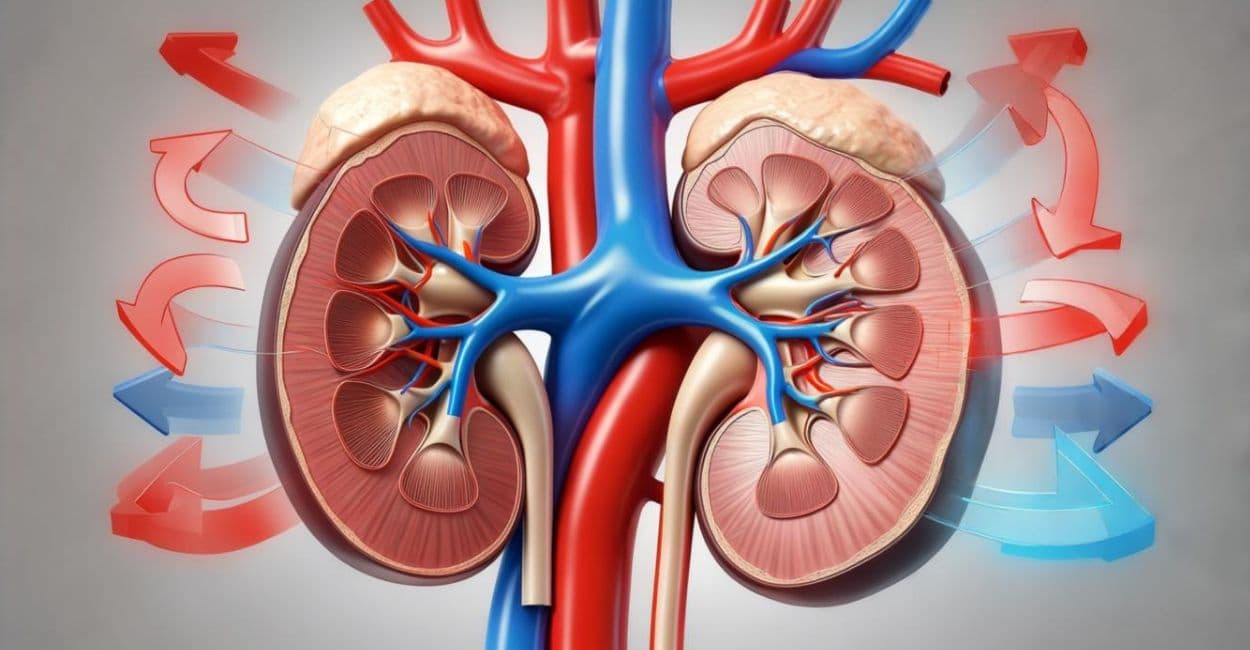

Descubra como a hemodiálise e diálise peritoneal substituem a função renal e mantêm a vida.

Entenda em detalhes o processo de filtragem do sangue, o rim artificial e cuidados vitais.